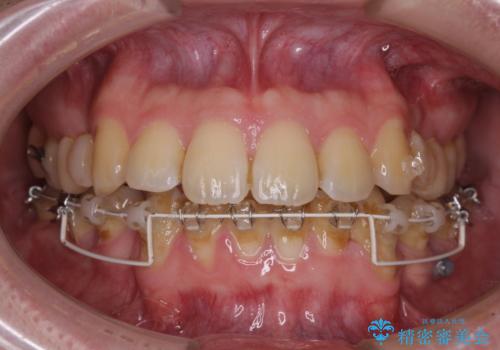

- 矯正装置

- ハーフリンガル

- 上顎の前突感による口の閉じにくさと八重歯を気にして来院された患者様です。

目立たない装置を希望されたので、上顎が裏側装置のハーフリンガルを選択し、上下左右の小臼歯(計4歯)を抜歯して矯正治療を行うこととしました。

上下顎で左右差の大きい抜歯矯正を裏側装置で行ったため、非常に時間がかかりましたが、正中位置も良い位置に改善され、気になっていた突出感も解消されました。